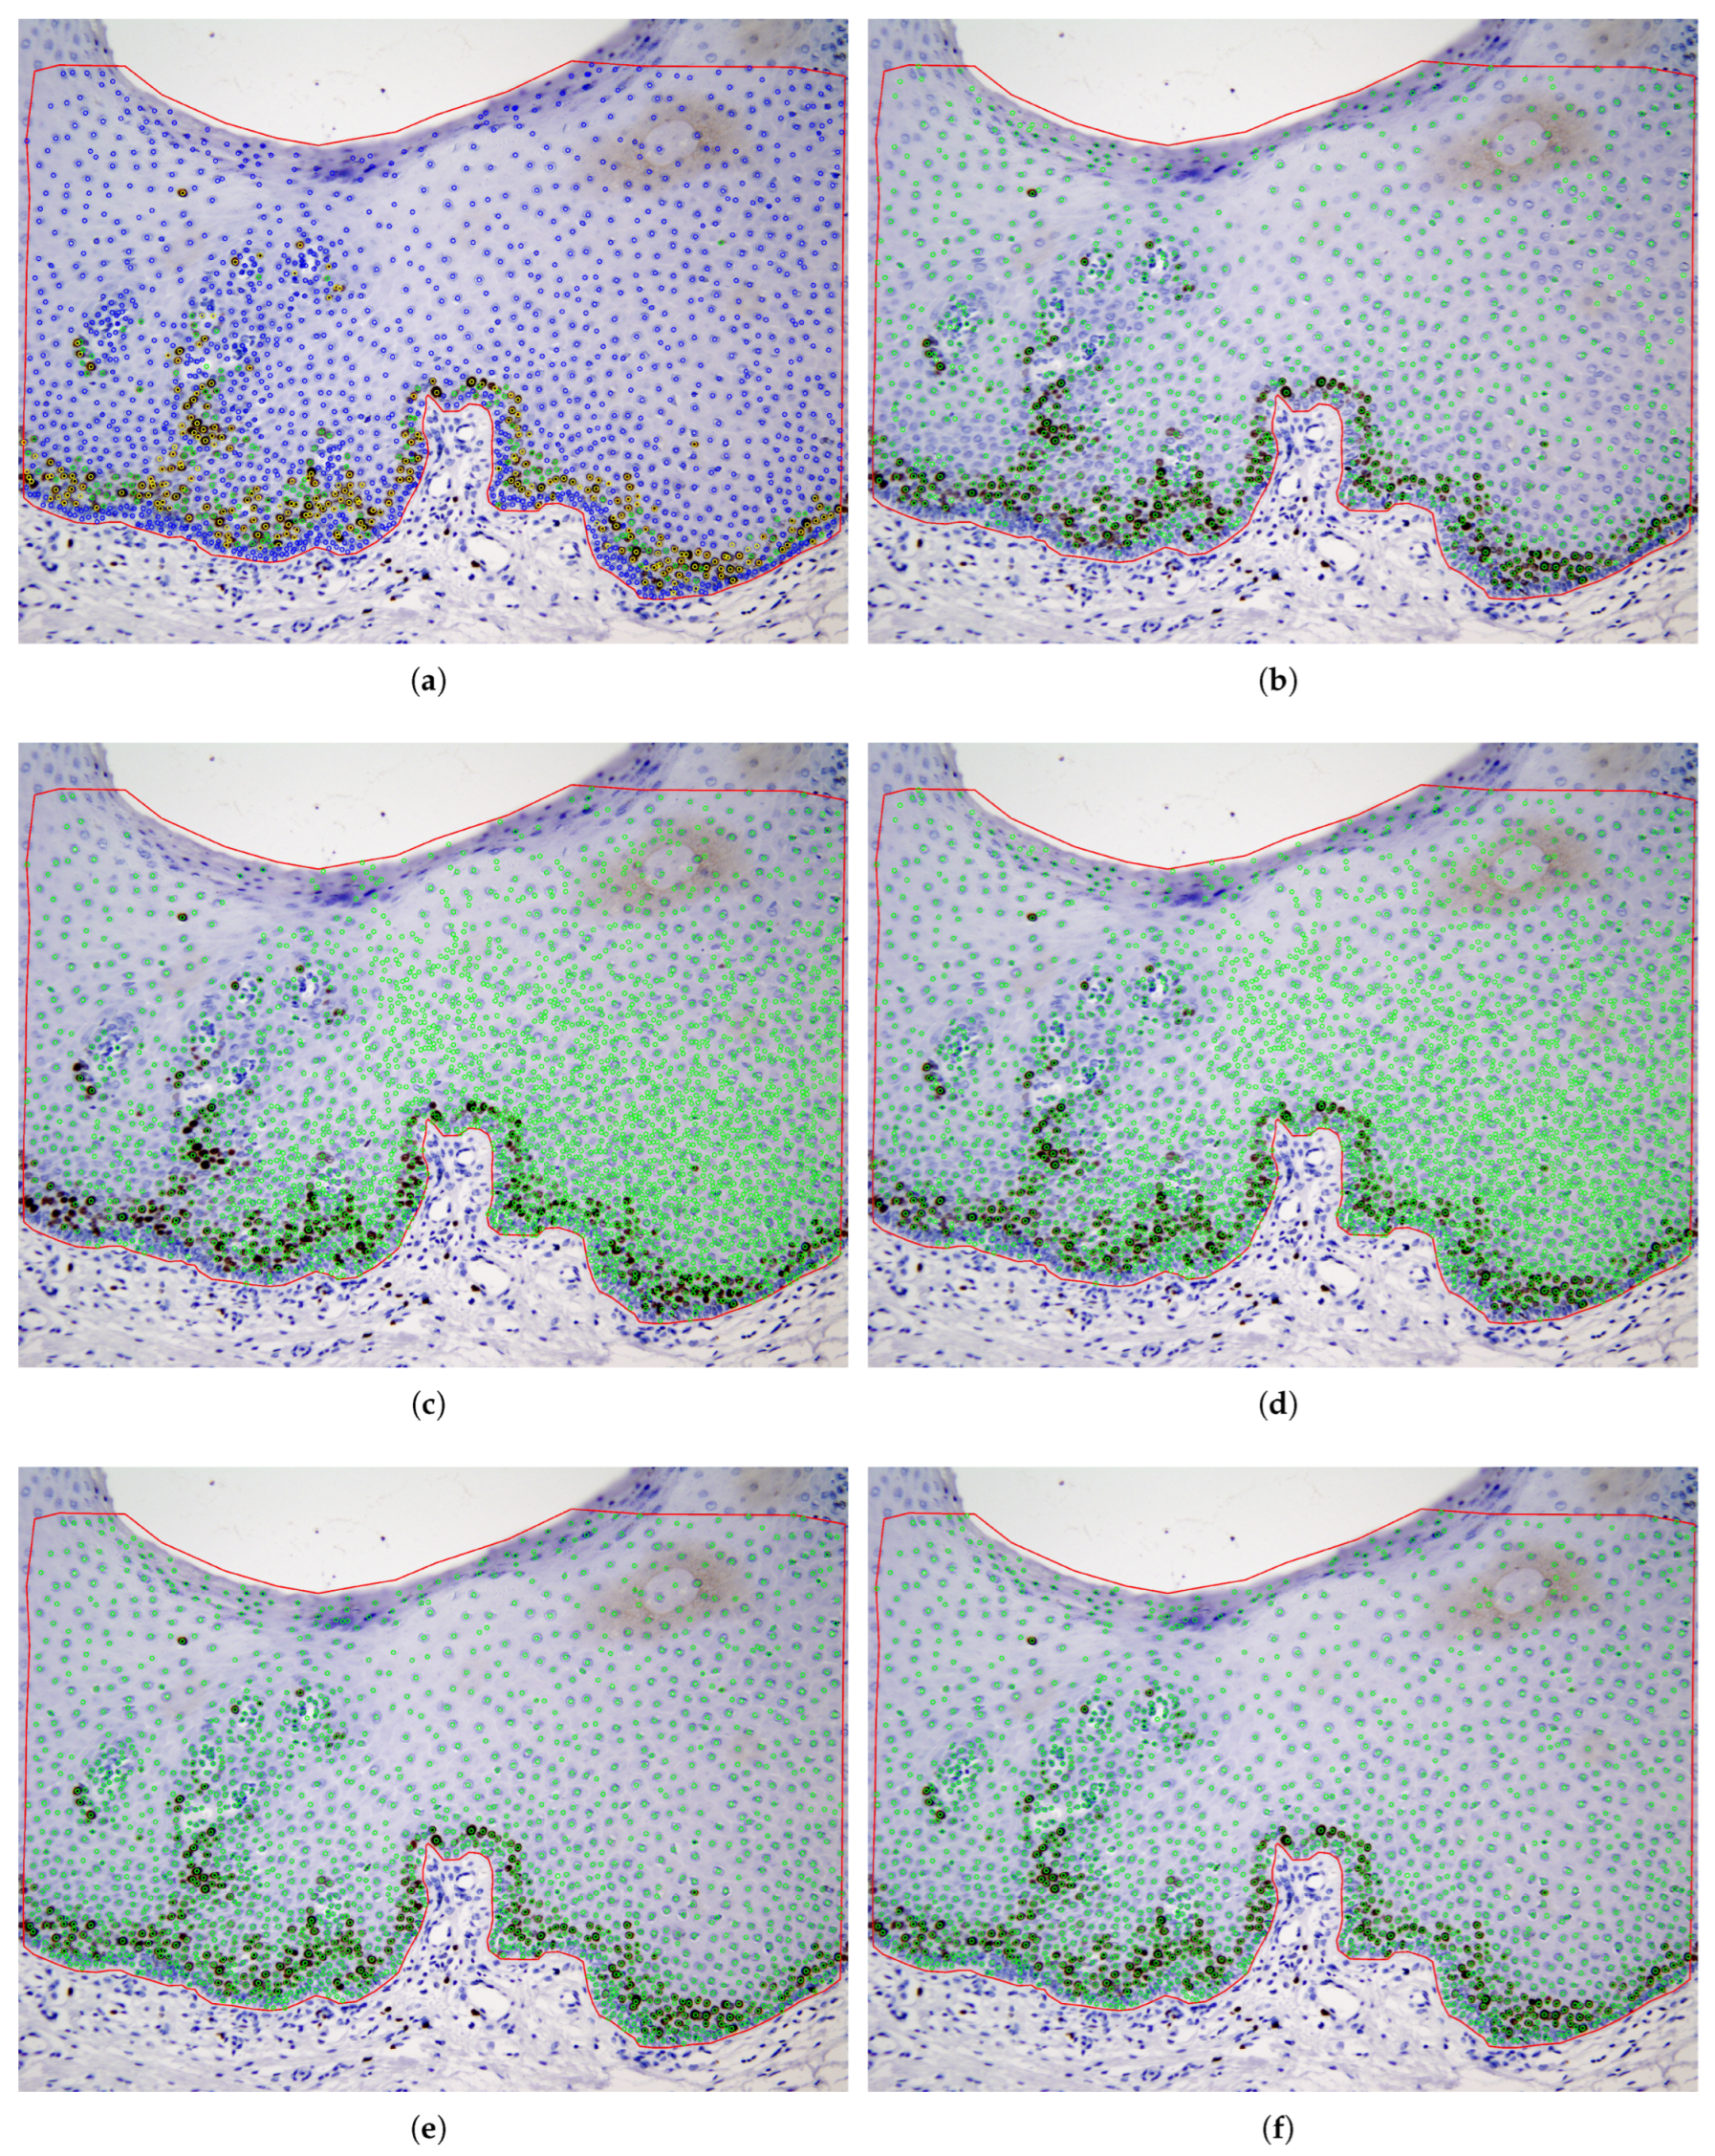

4.3. Cell Detection Using Unsupervised Segmentation